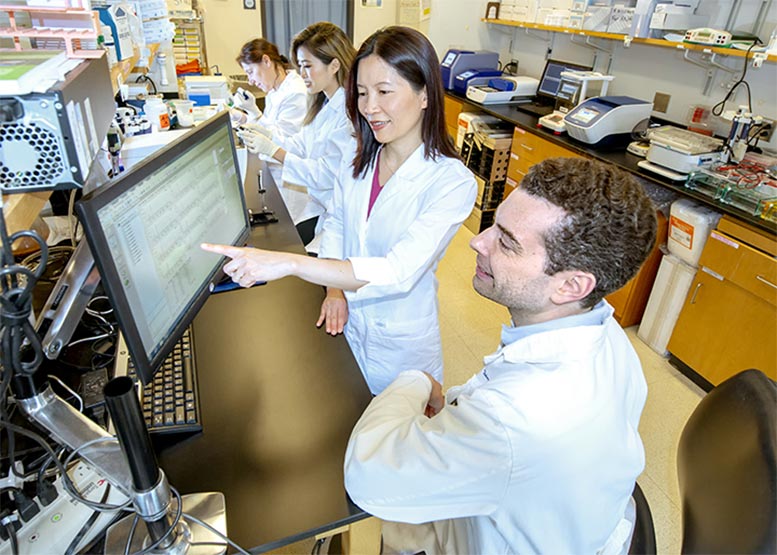

(Depressione-immagine: nel loro laboratorio presso l’Atlanta VA e la Emory University, il Dor. Thomas Wingo e la Dr.ssa Aliza Wingo (in primo piano) hanno trovato geni e proteine corrispondenti che potrebbero aprire le porte a nuovi trattamenti per la depressione. Credito: Lisa Pessin).

Wingo lavora con il Dr. Thomas Wingo, il primo autore dello studio, nel loro laboratorio congiunto presso l’Atlanta VA e l’Emory. Il laboratorio si concentra sulla comprensione delle basi genetiche delle malattie cerebrali. Hanno collaborato allo studio i ricercatori del Centro di malattie neurodegenerative di Emory.